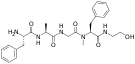

Opioid peptides

Enkephalins

Structures

| Enkephalins | ||||

|---|---|---|---|---|

DAMGO DAMGO |

||||

Propeptides

Others / unknown

- Adrenorphin

- Amidorphin

- Biphalin

- Casokefamide

- Casomorphins

- Cytochrophin-4

- DALDA (Tyr-D-Arg-Phe-Lys-NH2)

- Deltorphin I

- Deltorphin II

- Deprolorphin

- Dermorphin

- DPDPE

- Frakefamide

- Gliadorphin

- Gluten exorphins

- Hemorphin-4

- Metkefamide

- Morphiceptin

- Nociceptin

- Octreotide

- Opiorphin

- Rubiscolin

- Soymorphins

- Spinorphin

- TRIMU 5

- Tynorphin

- Valorphin

- Zyklophin

Structures

| Other or unknown opioid peptides | ||||

|---|---|---|---|---|

Adrenorphin Adrenorphin |

Amidorphin Amidorphin |

Casomorphin Casomorphin |

DALDA DALDA |

|

DPDPE DPDPE |

Endomorphin-1 Endomorphin-1 Endomorphin-2 Endomorphin-2 |

Gliadorphin Gliadorphin |

Morphiceptin Morphiceptin | |

Nociceptin Nociceptin |

Octreotide Octreotide |

Opiorphin Opiorphin |

Rubiscolin Rubiscolin |

TRIMU 5 TRIMU 5 |

Others